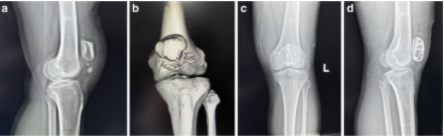

图3. 病例(例4,55岁,男性,右侧)。术前正位(A)和侧位(B) x线片显示髌骨下极移位骨折。术后正位(C)和侧位(D) x线片。2年随访时的x线片(E-F)和功能(G-I)。

图4. 病例示例(45岁,女性,右侧)。术前正位(A)和侧位(B) x线片显示髌骨下极移位骨折。术后正位(C)和侧位(D) x线片。术后19个月复查x线片(E、F)和功能(G-I)。